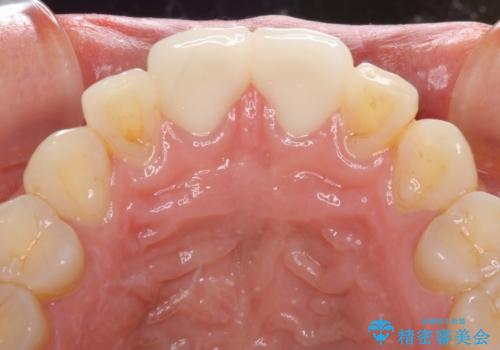

虫歯もない前歯を削ることは、処置をする者として心苦しいのですが、患者様は矯正治療は選択しないとのことだったので、オールセラミッククラウンにて補綴治療を行いました。

短期間で思い通りの仕上がりとなり、患者様には大変満足していただきました。